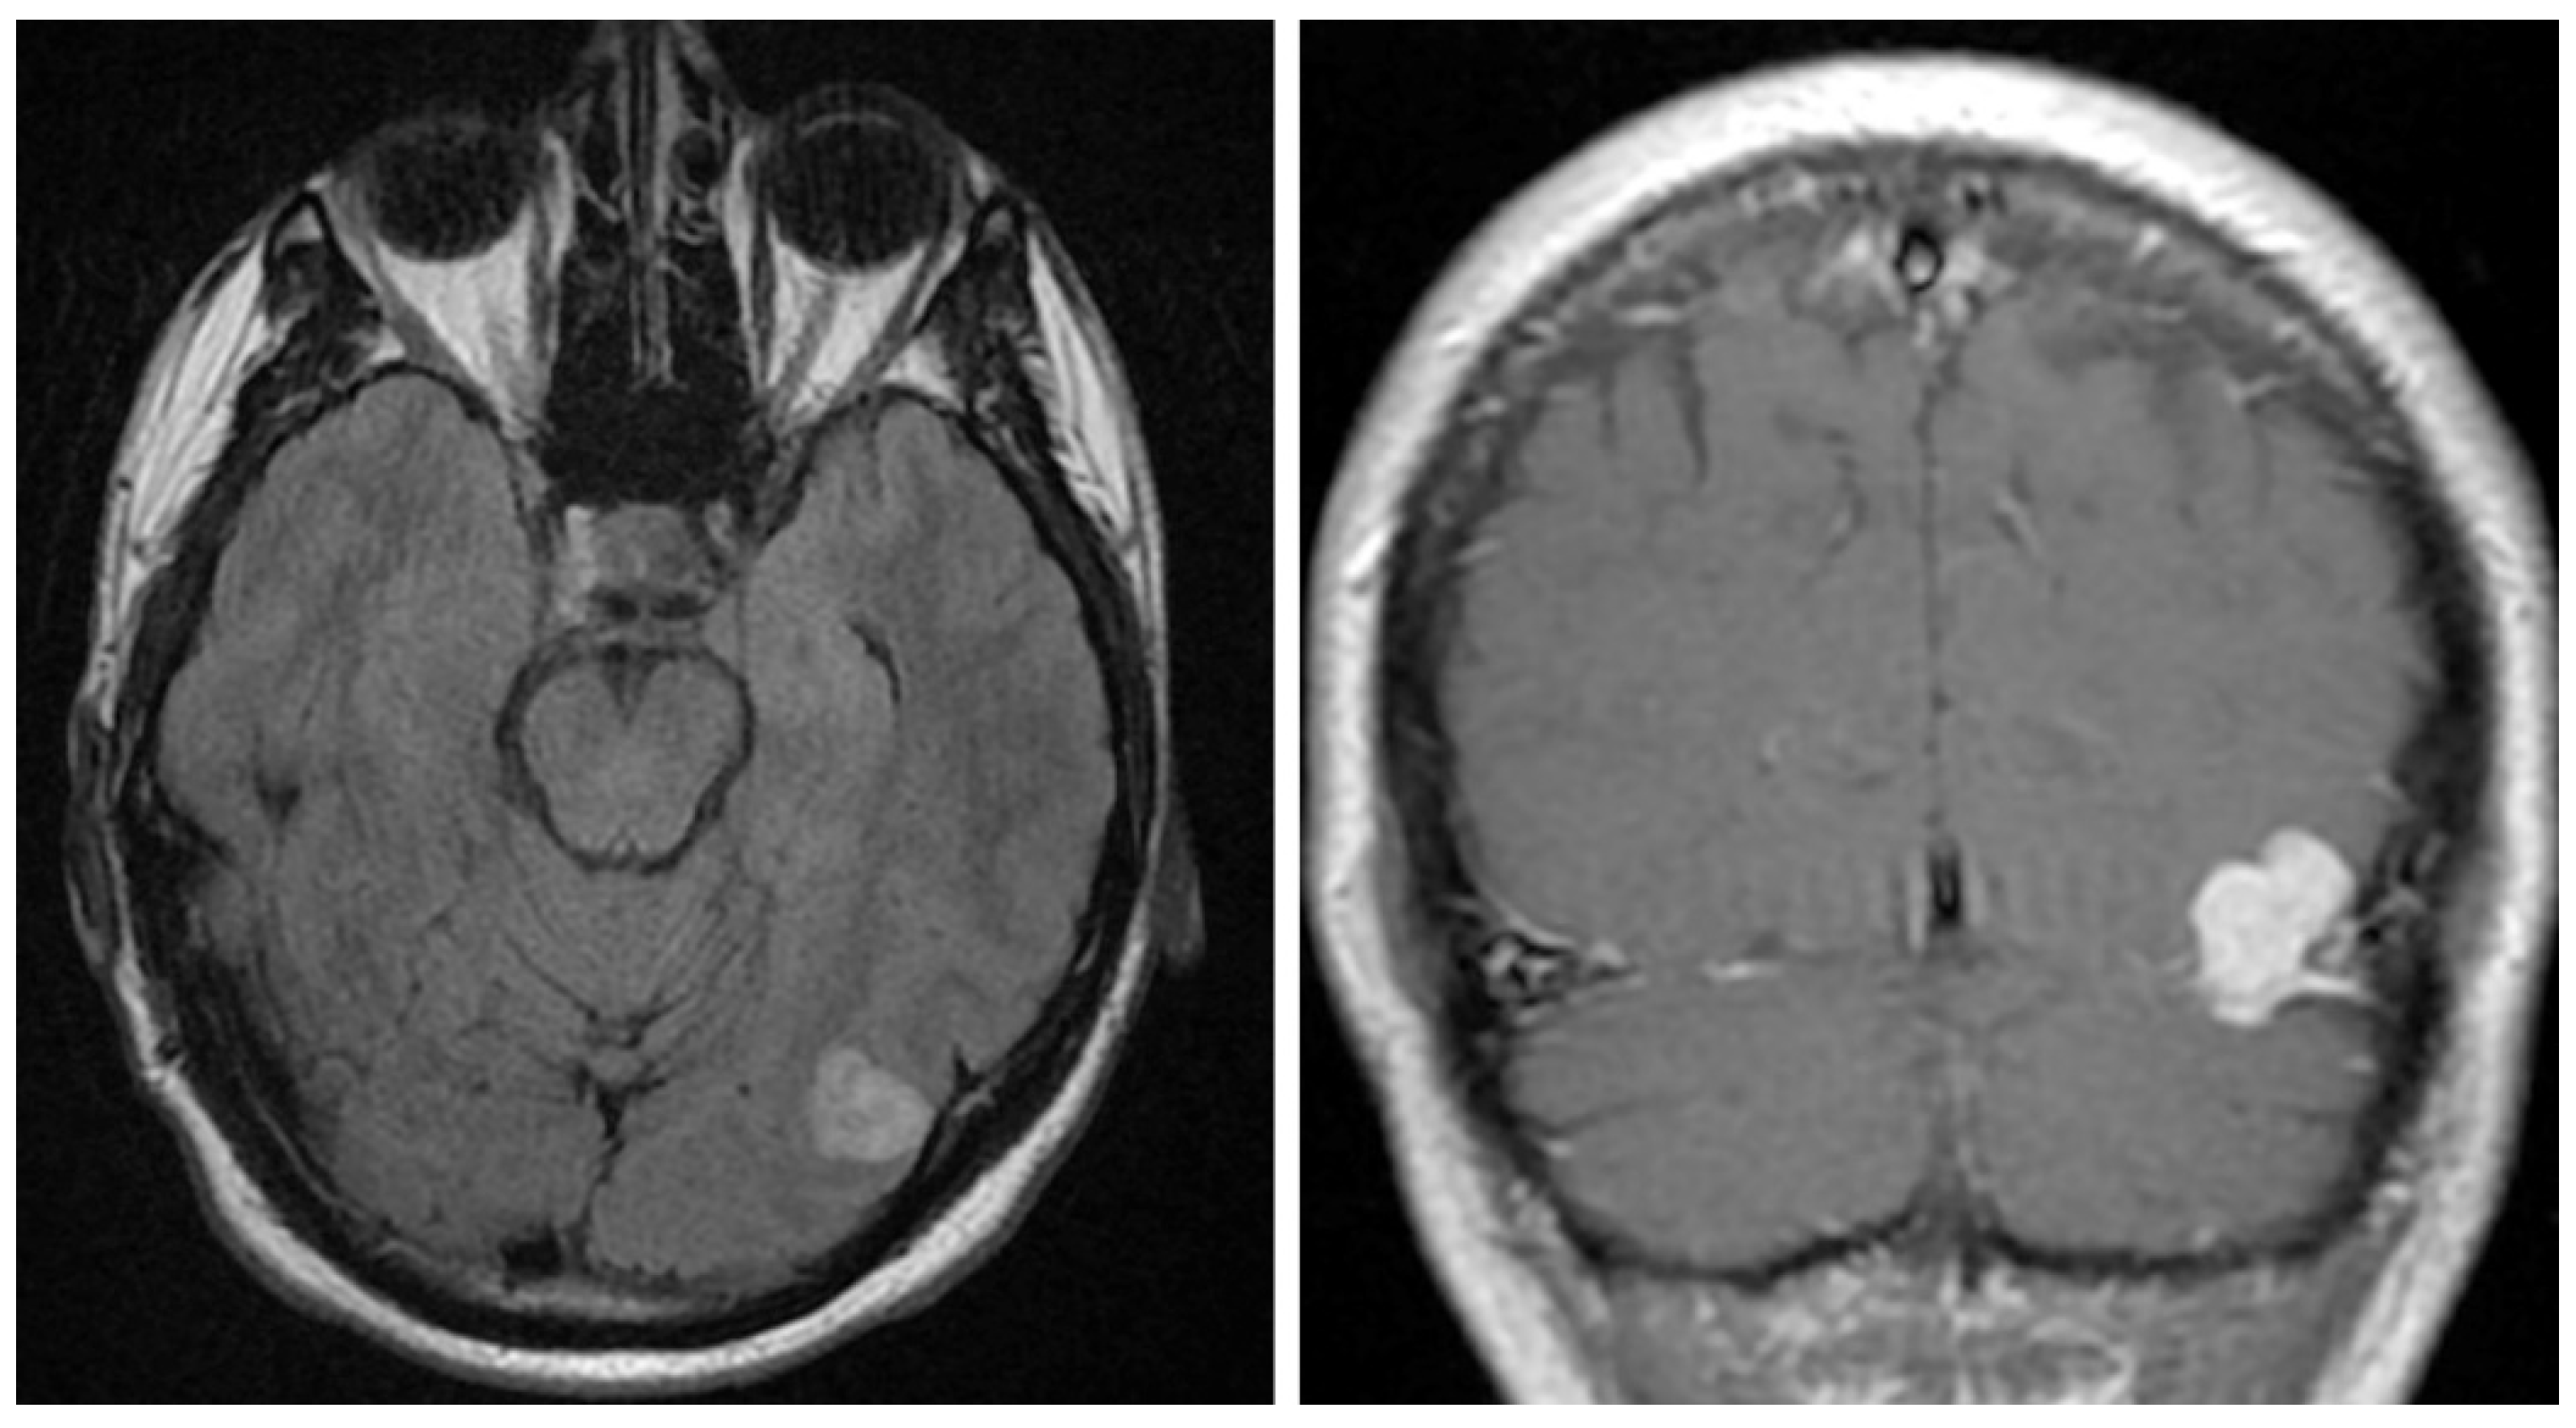

A 40-year-old gentleman presented for evaluation of several episodes of brief unresponsiveness, lasting approximately 30 seconds. The patient had a history of four seizure-like episodes after events like having his blood drawn, being in a hot tub, and hitting his knee. No family history of neurologic conditions was noted. The physical examination was unremarkable except for a slightly antalgic gait due to a recent ankle sprain. An unenhanced head CT demonstrated a 1.7 cm hyperdense nodule extending up from the left tentorium. Head MRI with and without contrast identified a 2.2 cm lobulated, mildly T2/Fluid attenuated inversion recovery (FLAIR) hyperintense, T1 isointense, homogeneously enhancing mass along the left tentorium (Figure 1). The lesion also showed small, punctate areas of hypo-intensity on susceptibility-weighted imaging. The differential diagnosis included meningioma and hemangiopericytoma (aka. Solitary fibrous tumor), given the FLAIR hyperintensity and hyperenhancement. The patient underwent a left craniotomy with a resection of the mass. Intraoperatively, the mass arose from the tentorium and extended posteriorly to the wall of the transverse sinus. The lesion was vascular in nature and resembled a cavernous angioma. The lesion was submitted for histopathological examination.

Figure 1.

Imaging studies. Head MRI with and without contrast identified a 2.2 cm lobulated, mildly T2/FLAIR hyperintense (left), T1 isointense, homogeneously enhancing mass along the left tentorium (right).